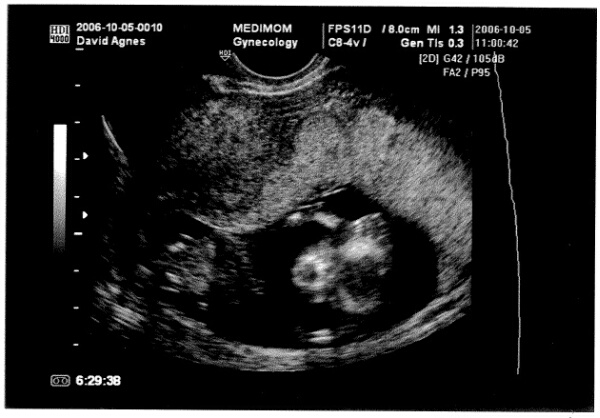

nos bemutatom ordító egeret:

Kép

a képen mindkét keze a feje előtt, a homlokánál az ujjai, felénk fordul, látni a száját, és a két szemét is, meg a nagy hasát

én E.T.-nek látom, az apja szerint az Alienre hajaz... :shock:

Vvviki, a beágyazódáskor én is barnáztam, és most nézd meg a képet :wink: :D